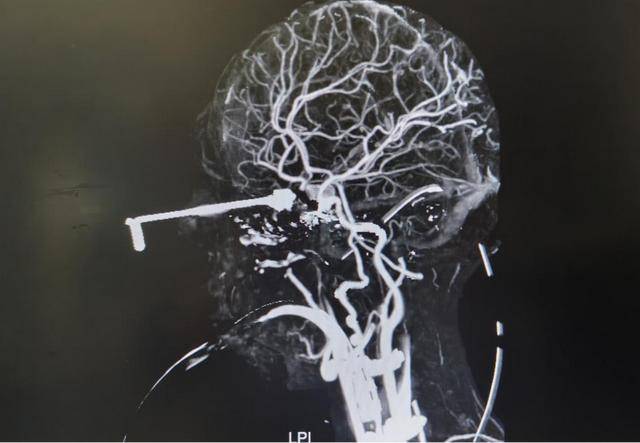

Theo thông tin từ bệnh viện, một bé trai 3 tuổi (tên đã được thay đổi) trong lúc chơi đùa đã vô tình cầm kim móc đan bằng kim loại – một vật dụng nhỏ, sắc và cứng. Khi người lớn không để ý, bé bị ngã, khiến đầu kim đâm xuyên từ vùng hốc mắt vào trong hộp sọ, gây tổn thương nghiêm trọng đến não bộ.

Ngay sau tai nạn, bé đau đớn khóc lớn, vùng quanh mắt sưng đỏ nhanh chóng. Đáng nói, loại kim móc này có cơ chế cánh mở, khi đâm vào sẽ mở ra, nhưng khi rút ngược ra, cánh khép lại, rất dễ móc vào mô mềm và mạch máu.

Do hoảng sợ và đau đớn, bé đã tự dùng tay rút chiếc kim ra khỏi đầu. Chính hành động này đã gây ra tổn thương thứ phát nghiêm trọng: mạch máu bị xé rách, xuất huyết não, dẫn đến nhồi máu não và biểu hiện yếu nửa người.

Các bác sĩ cho biết, ca phẫu thuật gắp dị vật vô cùng phức tạp vì kim đã dính chặt vào các mạch máu và dây thần kinh quan trọng. Ê-kíp phẫu thuật buộc phải thao tác cực kỳ cẩn trọng để tránh gây chảy máu ồ ạt hoặc tổn thương không hồi phục.

Rất may, sau nhiều giờ phẫu thuật, dị vật đã được lấy ra an toàn, không xảy ra biến chứng nghiêm trọng. Hiện tại, tình trạng của bé ổn định, thị lực được bảo toàn, các dấu hiệu yếu liệt do nhồi máu não đang dần cải thiện và bé đã bước vào giai đoạn phục hồi chức năng.